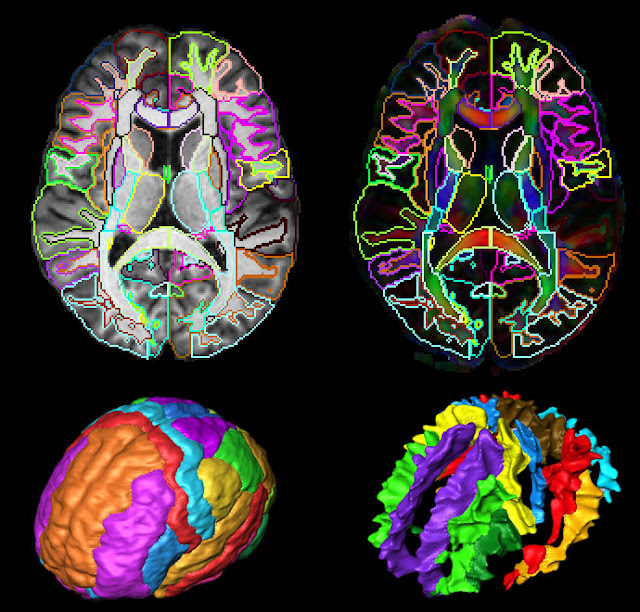

brain imaging png

Laboratory Of NeuroImaging

Brain Imaging